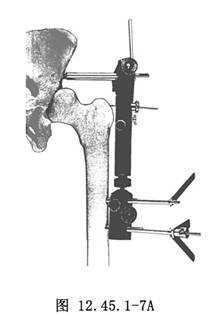

7.依據模板,擰入股骨的半徑針。擰入股骨半徑針時應將模板向前屈曲15°(相對於股骨軸線),爲了得到最大的穩定性,應選用模板上的第1和第5孔(圖12.45.1-7A)。全部半徑針擰入後,取掉模板和導針,將外固定架固定到上述半徑針上,擰緊固定螺栓,最後用扭矩扳手鎖緊萬向軸的凸輪(圖12.45.1-7B)。